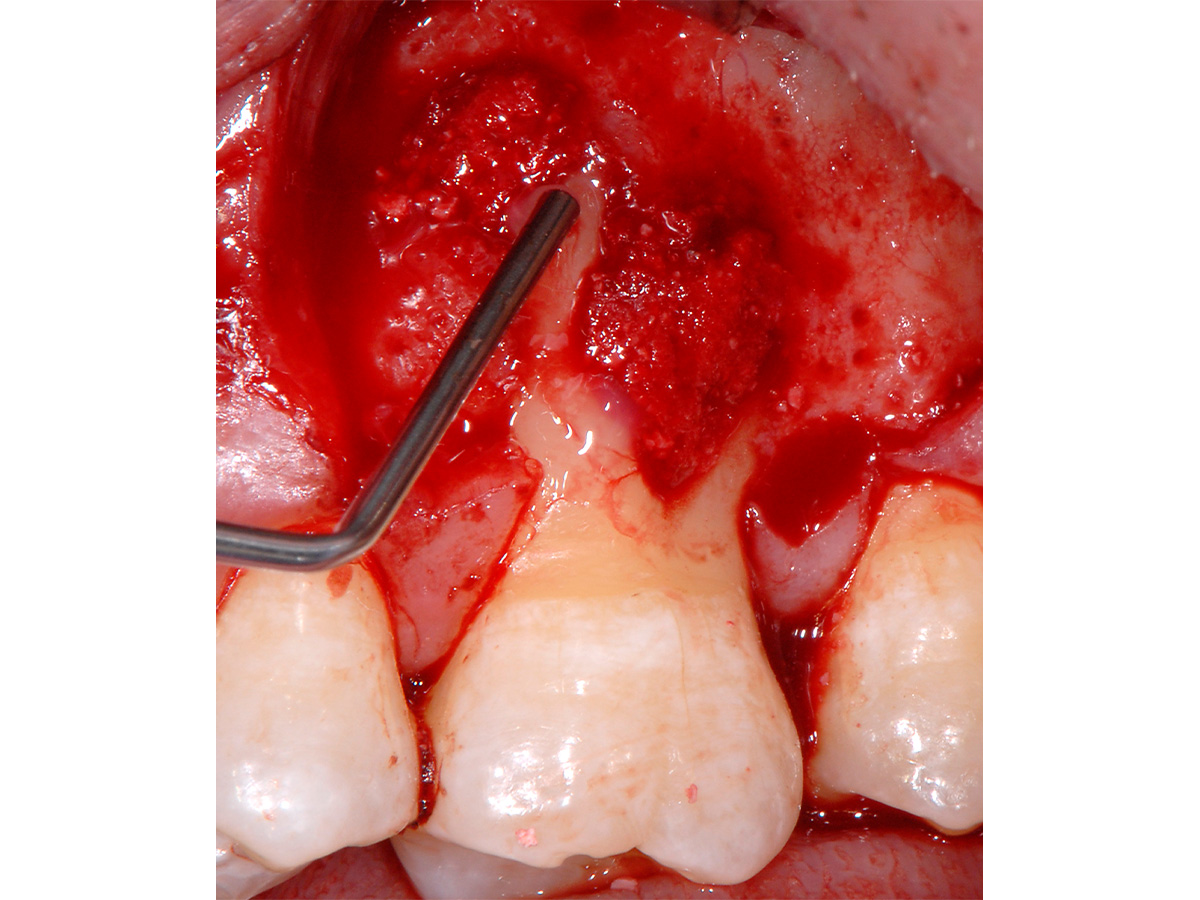

Abbildung 3

Mikrochirurgischer Zugang mit Schonung der interproximalen Bereiche. Vorbereitung dort durch Entepithelisierung zur späteren koronalen Verschiebung der bukkalen Lappenanteile.